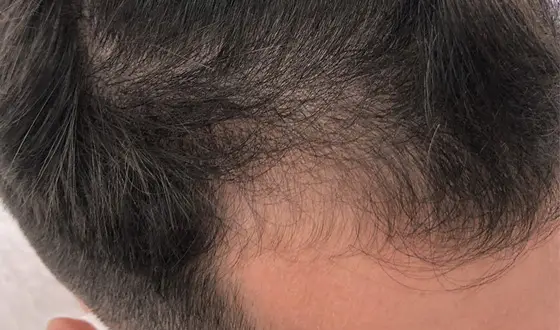

Plasma Rico em Plaquetas de 5 sessões

Após 6 meses

Após 6 meses

Plasma Rico em Plaquetas de 3 sessões